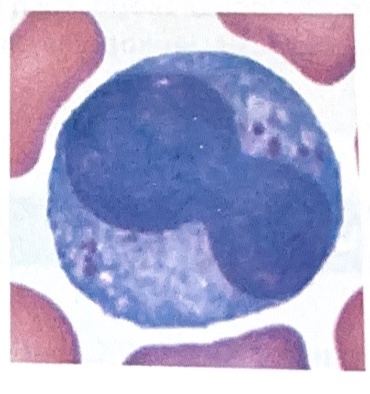

Lymphocytes

Slightly larger that RBC’s

Thin rim of nearly clear cytoplasm

Nearly round nucleus appears to fill most of cell in smaller lymphocytes

Larger lymphocytes hard to distinguish from monocytes